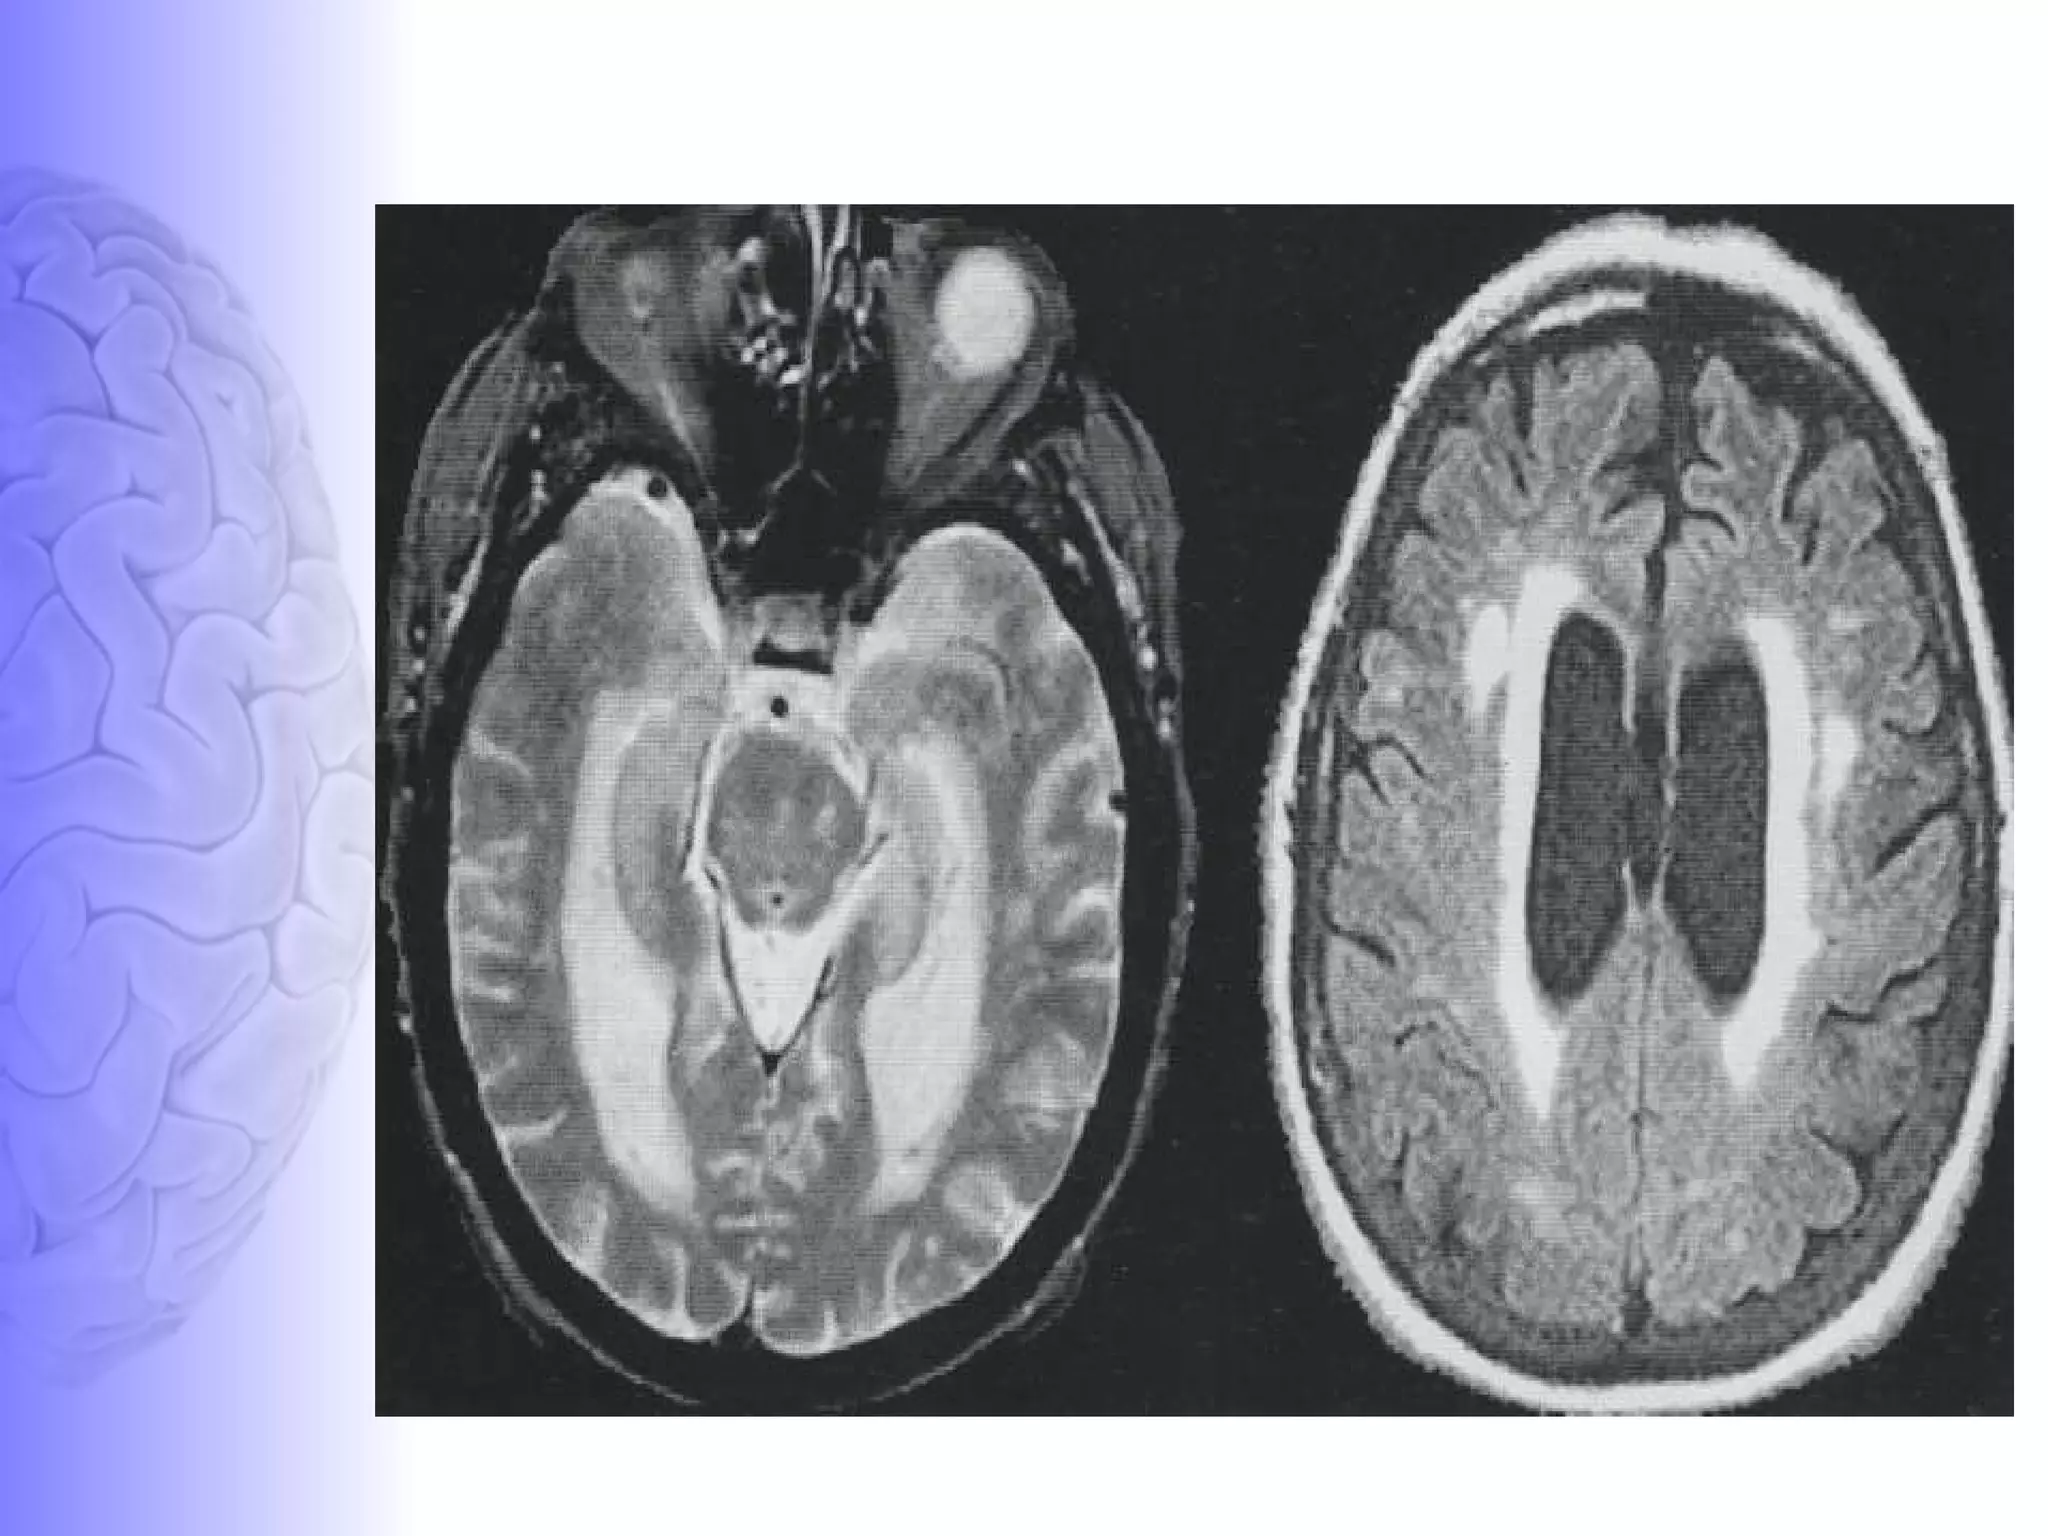

MRI features of FTD MR features :  Severe sharply localized atrophy- bilaterally symmetric-  “knife-blade atrophy.”  Hyperintense signal in the cortex and underlying white matter of the affected areas. Areas involved : frontal lobe, anterior temporal lobes, extra pyramidal nuclei especially the caudate nucleus, insular cortex & anterior corpus callosum. Areas spared : Posterior two thirds of the superior temporal gyrus, occipital lobes, parietal lobes & perirolandic region These  MR findings  in an  appropriate clinical setting  may support the diagnosis of FTD.

MRI features ofFTD MR features : Severe sharply localized atrophy- bilaterally symmetric- “knife-blade atrophy.” Hyperintense signal in the cortex and underlying white matter of the affected areas. Areas involved : frontal lobe, anterior temporal lobes, extra pyramidal nuclei especially the caudate nucleus, insular cortex & anterior corpus callosum. Areas spared : Posterior two thirds of the superior temporal gyrus, occipital lobes, parietal lobes & perirolandic region These MR findings in an appropriate clinical setting may support the diagnosis of FTD.